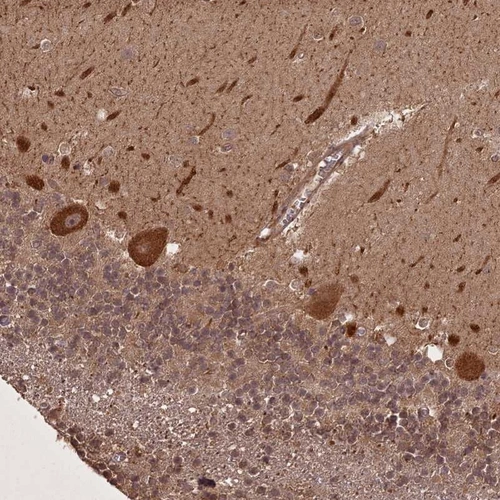

Immunohistochemical staining of human cerebellum shows strong cytoplasmic positivity in Purkinje cells.